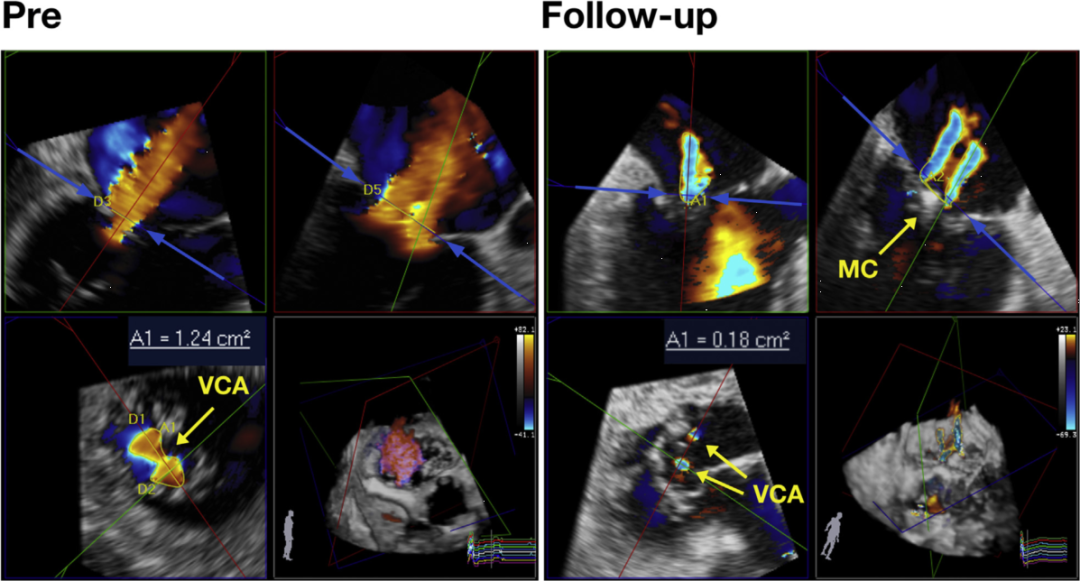

VCA的面积测量示例。同一患者中,在MitraClip(MC)前不对称VCA(1.24cm²)的面积测量以及术后随访被MitraClip(MC)隔开的两个VCA(总计0.18cm²)